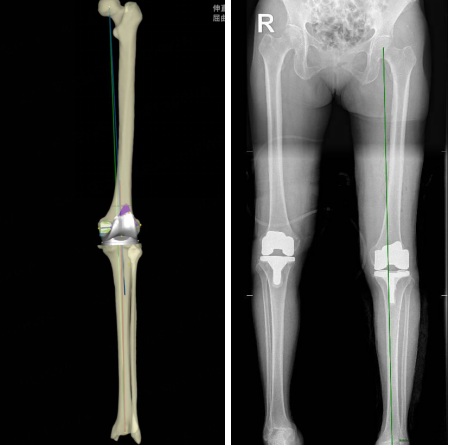

患者术前影像及术前规划

科室团队术前为患者进行了患肢全长CT扫描,将CT数据导入骨科机器人软件系统中,机器人智能提取患者CT数据并进行三维重建,选择出适合的人工关节假体型号,规划出最佳截骨厚度、方向和角度,提前为患者制定个性化、精确化的术前计划。

手术在骨科关节机器人的辅助下顺利完成,术前规划的假体大小、角度和位置均与术中实际应用一致,内外侧间隙及屈伸间隙平衡,髌骨轨迹及关节活动度良好,术后复查X线片提示假体位置良好,下肢力线恢复至中立位。

患者术后左侧下肢全长片与术前规划一致

乐国平主任介绍,传统的关节置换手术操作更依赖于医生的经验,一旦操作出现偏差,就容易导致力线改变,影响手术效果。关节机器人是集临床医学、生物力学、机械学、材料学、计算机科学、微电子学、机电一体化等诸多学科为一体的现代尖端科技医用设备。该机器人机械臂和刀具的一体化和集成化设计,降低了传统手术操作中可能出现的误差,能有效提高手术质量,给临床带来更高的手术精度,更稳定的手术发挥,更流畅的手术操作,真正实现了智能化人机互动。特别对于合并股骨或胫骨畸形的复杂病例,治疗过程中无需在畸形处截骨,只需一次手术就可以达到治疗效果,保证了下肢力线的有效矫正和双下肢力线的对称性,以及截骨的准确性。